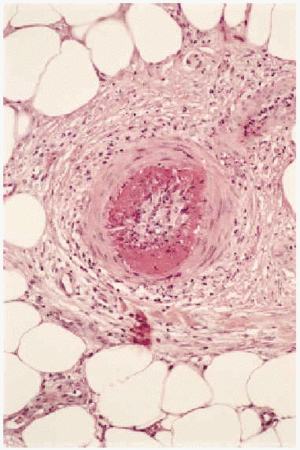

Desde el punto de vista anatomopatológico podemos encontrar hallazgos histológicos típicos de vasculitis leucocitoclástica o signos de poliarteritis nudosa (PAN). El momento más adecuado para realizar la biopsia es a las 24 a 48 horas de la aparición de las lesiones. En la vasculitis leucocitoclástica hay afectación de vaso pequeño (arteriolas, vénulas y capilares) y la arquitectura vascular está alterada por un infiltrado inflamatorio mixto que rodea los vasos e incluso penetra en ellos (fig. 4). Las células endoteliales se muestran prominentes y la presencia de leucocitoclasia y extravasación hemática puede completar el cuadro. Debemos recordar que la leucocitoclasia es un dato no específico, que simplemente revela un infiltrado neutrofílico importante y puede verse en otras entidades como el síndrome de Sweet o diversas infecciones cutáneas. La PAN afecta vasos medianos y pequeños, con presencia de necrosis fibrinoide y un infiltrado inflamatorio mixto de monocitos, linfocitos y polimorfonucleares neutrófilos que interrumpen y borran la arquitectura vascular (fig. 5)19. La presencia de trombos de aspecto hialino, eosinófilos, PAS positivos, ocluyendo la luz de los vasos, aunque muy típica, no es muy frecuente salvo en la CGM tipo I (fig. 6), en la que coinciden con criocritos muy elevados, mientras que las alteraciones de vasculitis, especialmente en las CGM tipo II, son más frecuentes con criocritos bajos. Este fenómeno continúa aún sin explicación, aunque parece deberse a la capacidad intrínseca de los inmunocomplejos de activar el complemento in situ.

Fig. 6.--Vasos ocluidos por trombos eosinófilos de aspecto hialino, característicos de las crioglobulinemias.